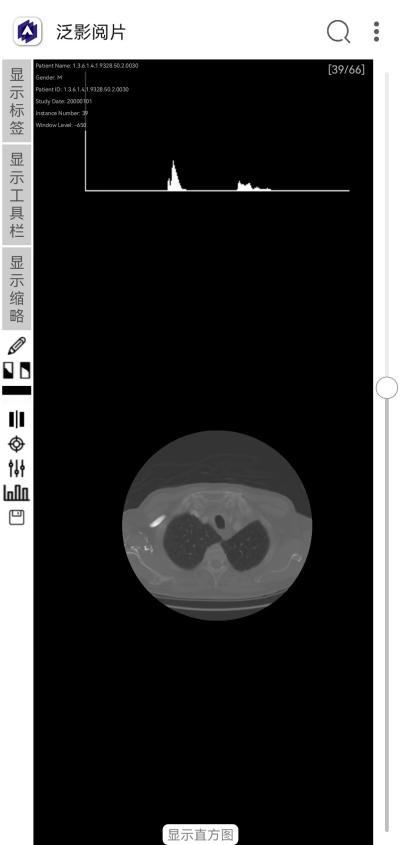

显示直方图。以直方图形式显示出DICOM图像的统计信息。